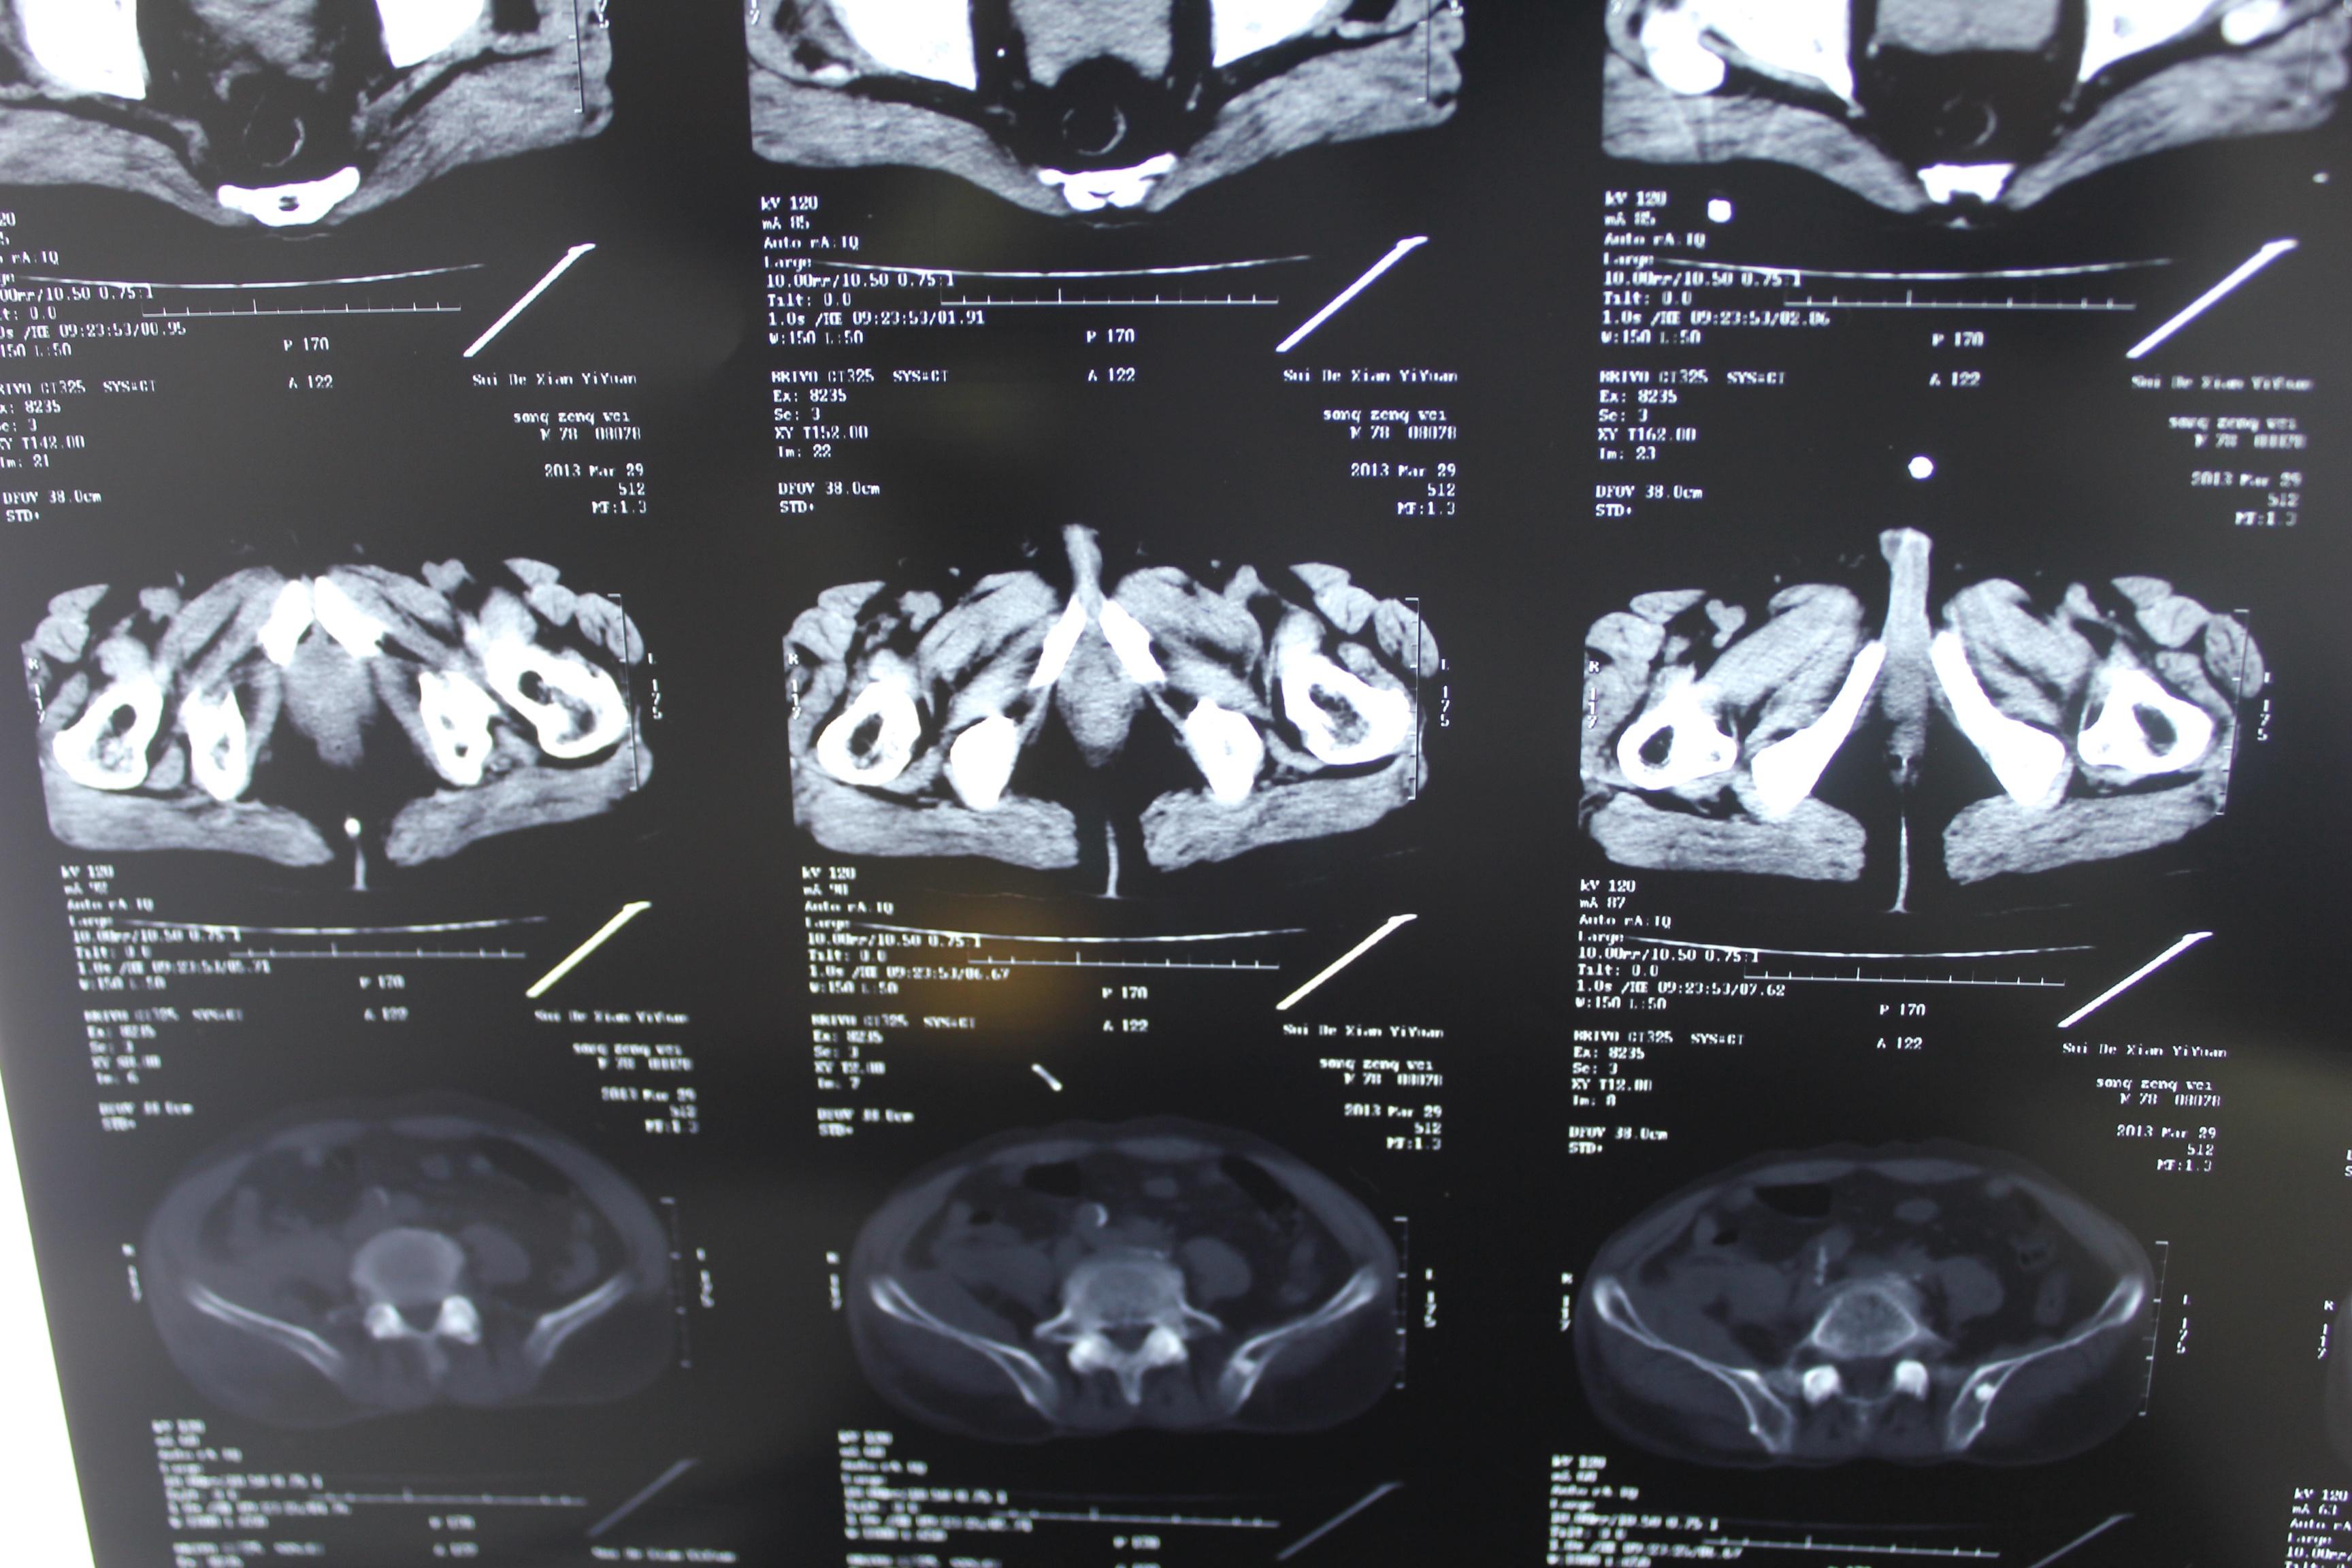

老年患者78岁,反复腰背部溃烂流脓4年,既往30年前曾在包块处排出蛔虫一条。CT: